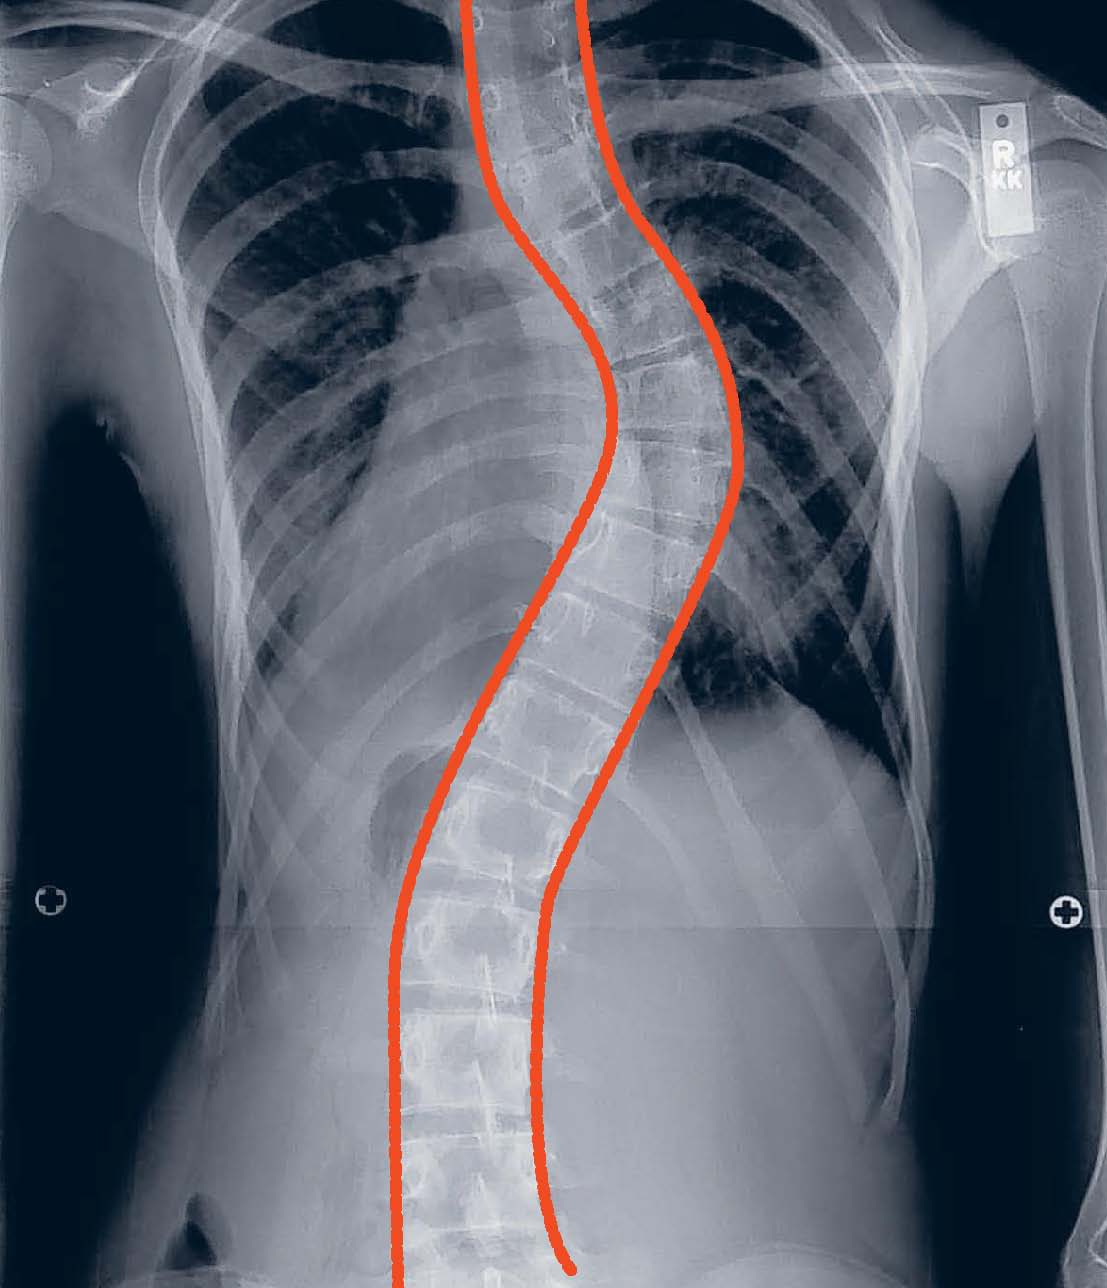

3 most common causes & types of curved spine and the treatments

3 most common causes & types of curved spine and the treatments Curved Back Surgery Scoliosis is a lateral (or sideways) curvature of the spine in one or more places. The goal of this surgery is to realign the curved areas of the spine, fusing metal rods or pieces of bone together to form a new, straighter, solid section of spine. Scoliosis surgery, also known as spinal fusion surgery, is performed to correct curvature of. Curved Back Surgery.